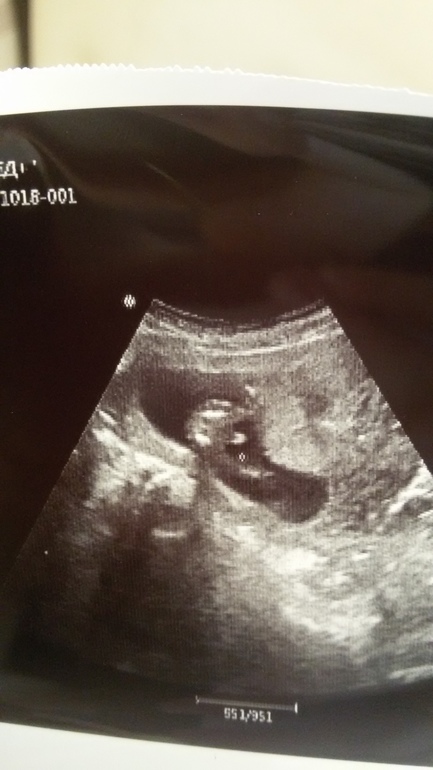

Пол малышаСходили мы сегодня на узи для моего успокоения и с небольшой надеждой узнать пол. Сначала нам сказали, что ничего мальчукового не видно, а потом узистка говорит что вот что-то появилось😆Ножки раскинул . Девочки подскажите как думаете это хозяйство между ножек?)

У нас похожий снимок на 13 недельке, узист с гарантией 60%

предположил мальчика, хотя может это и пуповина сказал. В 17 недель подтвердился мальчишка)

Если на фото сидит на попе, то мальчик. У меня просто такое же фото имеется моего мальчика)